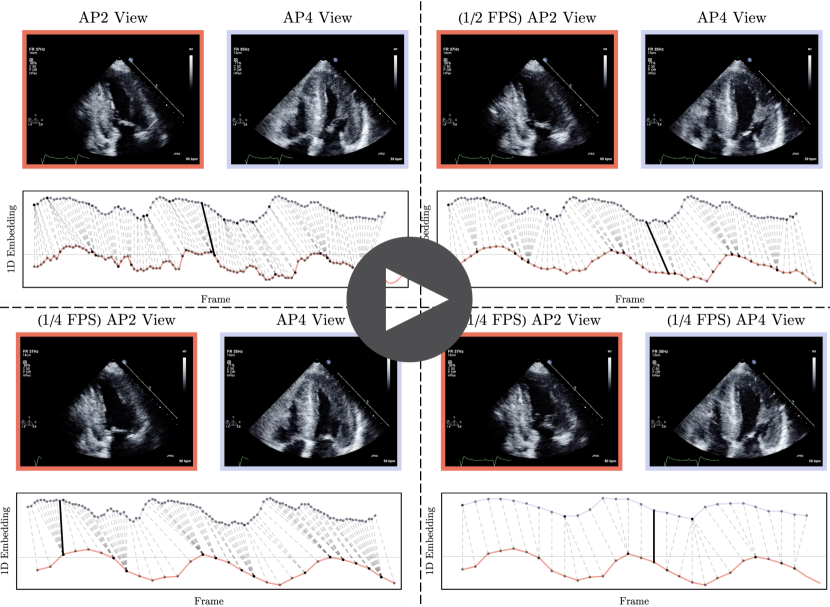

Refer to caption

Figure 14: A screenshot of synched cines captured from AP4 and AP2 views along with their trajectories in the embedding space. This experiment shows the robustness of the proposed synchronization method to different frame rates. We first produce downsampled versions of both cines at one-half and one-quarter of their original frame rate. Next, we create embeddings and perform synchronization using various combinations of original, half sampled and quarter sampled pairs. It should be noted that we reduced the embeddings’ dimensions from 128 to 1 using principal component analysis for better visualization.